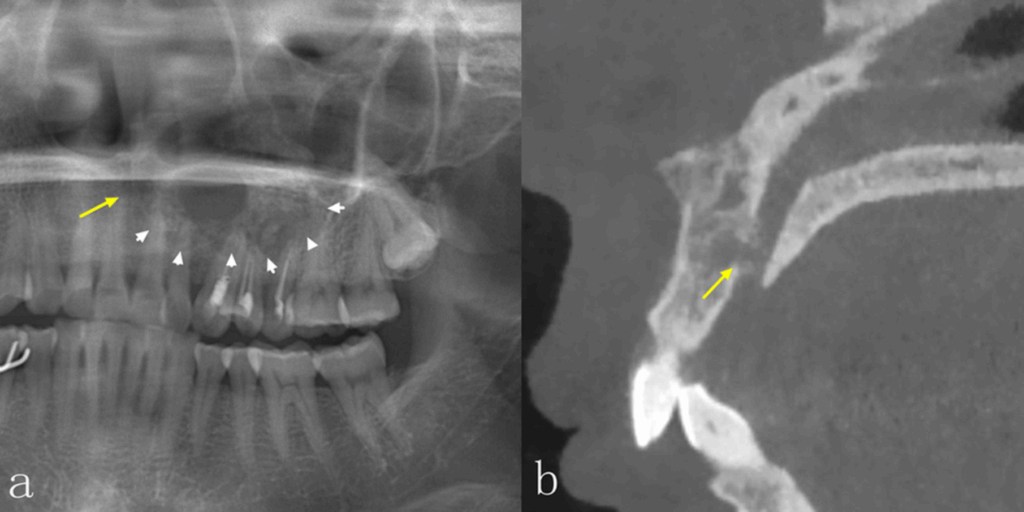

Comparación entre la precisión diagnostica de la radiografía panorámica y la tomografía computarizada de haz cónico

La radiografía panorámica (PAN) y la tomografía computarizada de haz cónico (TCCB) son dos modalidades radiográficas utilizadas en el diagnóstico, la planificación del tratamiento y el manejo de las enfermedades orales y maxilofaciales. No solo muestran las características de las lesiones en las imágenes, sino que también guían a los médicos para que realicen los...